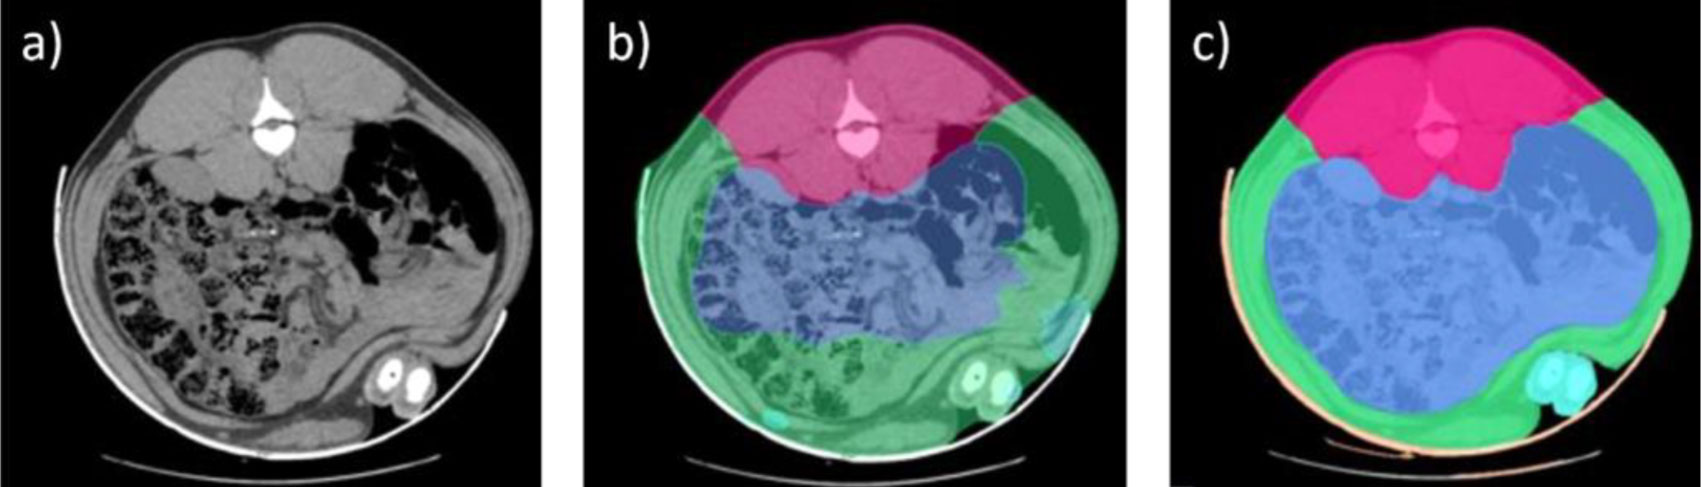

O processo de análise das imagens foi realizado durante anos de forma manual, identificando as diferentes áreas anatômicas e tipos de tecidos (osso, gordura e músculo), o que já representou um avanço significativo. Em 2016, foi implementado um primeiro método mais automático de análise de imagens de TC, que permitia distinguir entre as principais partes (presunto, paleta, lombo e panceta). O surgimento das tecnologias de Inteligência Artificial (IA) foi fundamental para a automatização desse processo, essencial para ampliar o uso dessa ferramenta e aumentar o número de animais analisados de forma mais eficiente.

No entanto, a IA requer um processo prévio de treinamento, para o qual é necessária uma base de dados extensa com imagens previamente analisadas que sirvam de modelo. No nosso caso, essa base de dados estava disponível graças aos anos anteriores de análises com TC, durante os quais já se havia avançado significativamente na segmentação dos tecidos e na identificação, na imagem, dos voxels (as menores unidades que compõem uma imagem tridimensional, semelhantes aos pixels em uma fotografia) que pertencem a diferentes tecidos.